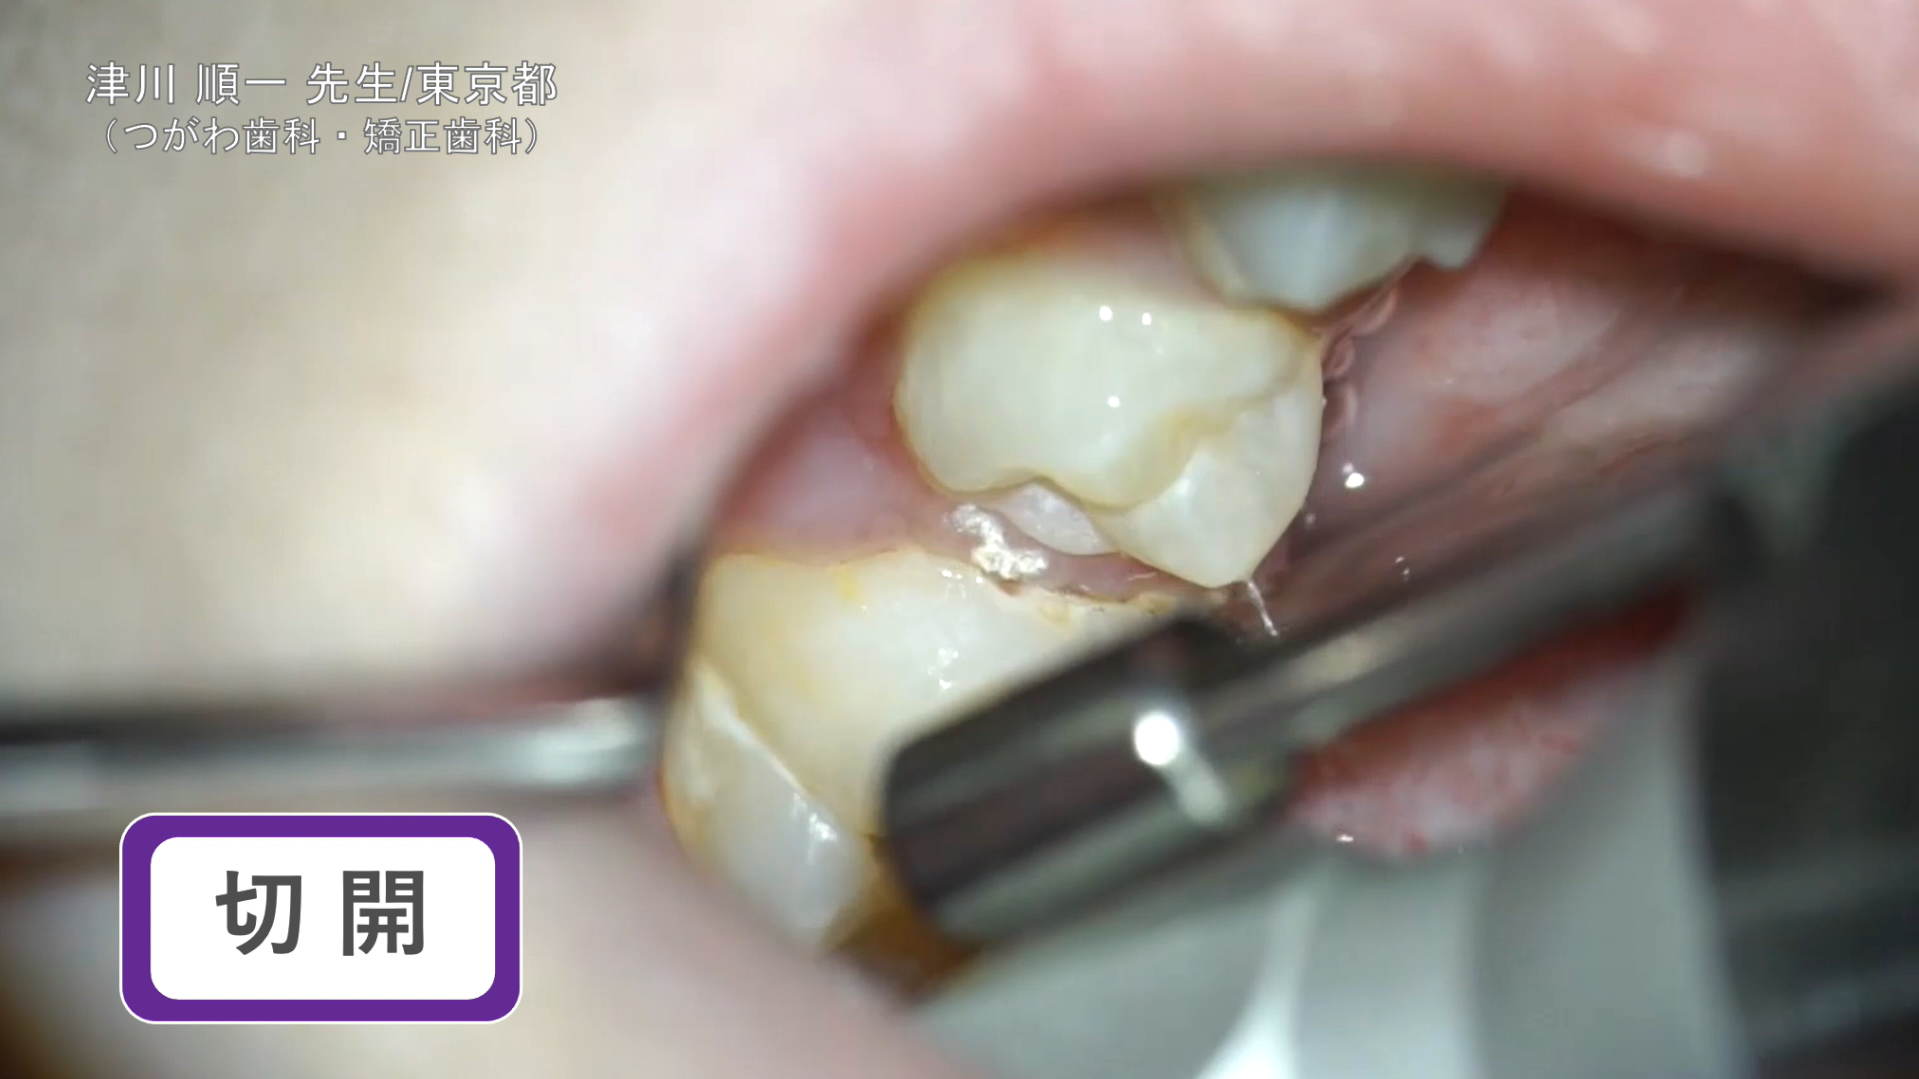

切開

臨床例:炭酸ガスレーザーPRO+/Lite+(最大出力5~7W)を使用した先生の臨床例です。